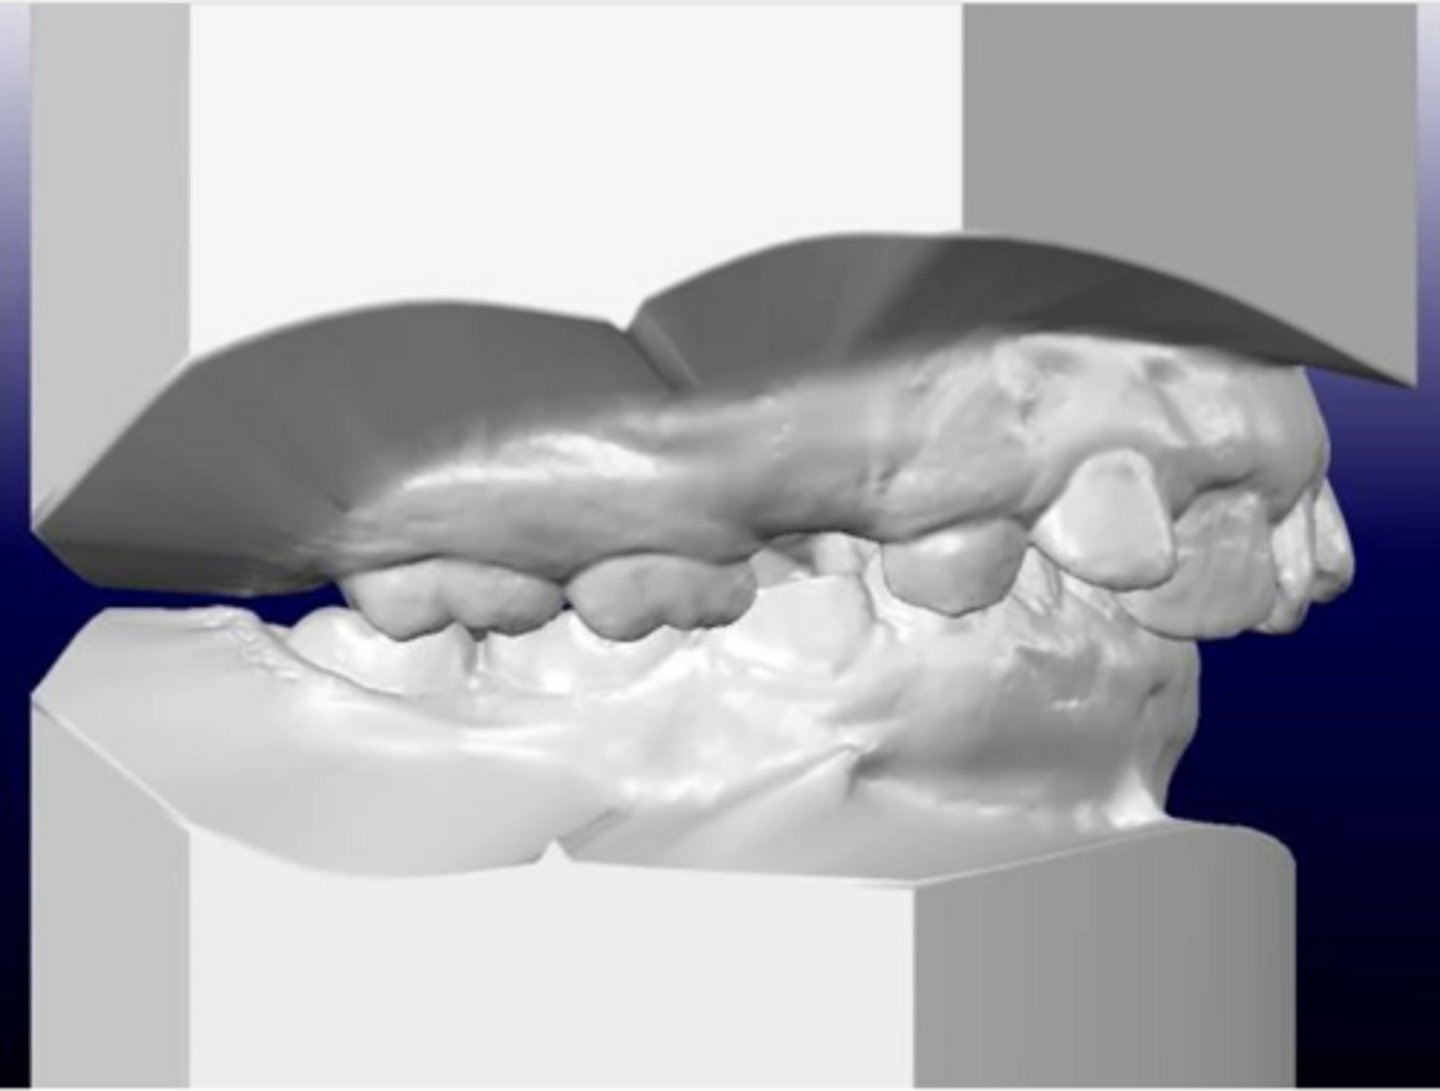

Class II, Subdivision Right

(On the left, she is Class I. On the right, she is Class II. "Class II, Subdivision Right" describes this.)

What type of malocclusion does this patient have?

Premature loss of a molar, which might have caused the shift on just the one side

What might have caused her malocclusion?